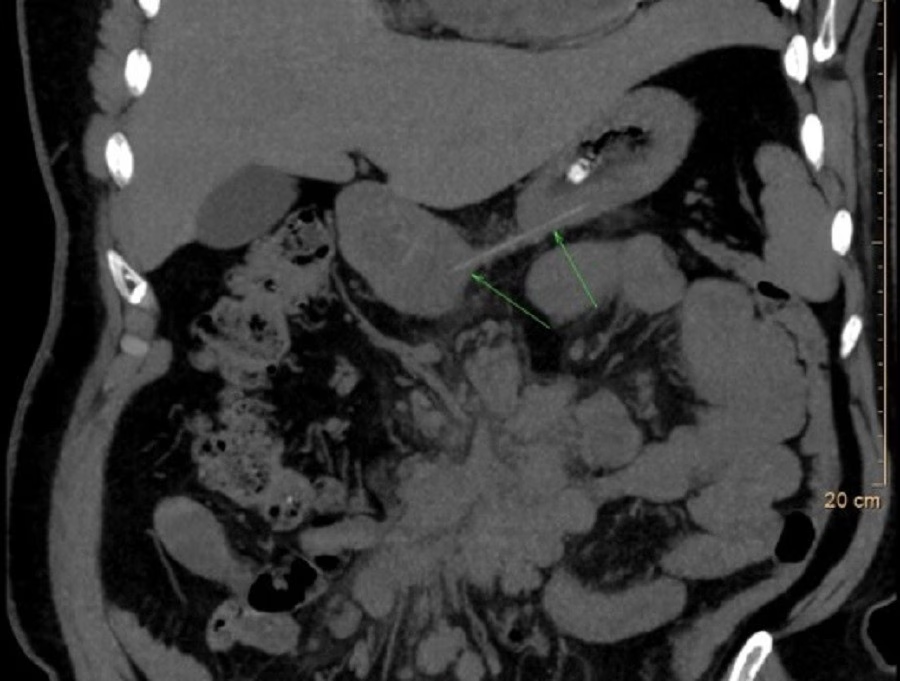

Nội soi thanh quản cho thấy sụn thanh và sụn phễu phù nề nghiêm trọng, che lấp gần như toàn bộ đường thở. CT xác nhận phù nề nặng ở thanh thiệt, sụn phễu và đáy lưỡi, tạo nguy cơ tắc nghẽn đường thở cao. Bệnh nhân được nhập viện, nội soi lấy dị vật, kết hợp kháng sinh, kháng viêm, phun khí dung và giảm đau. Sau điều trị, phù nề giảm dần và triệu chứng cải thiện rõ rệt.